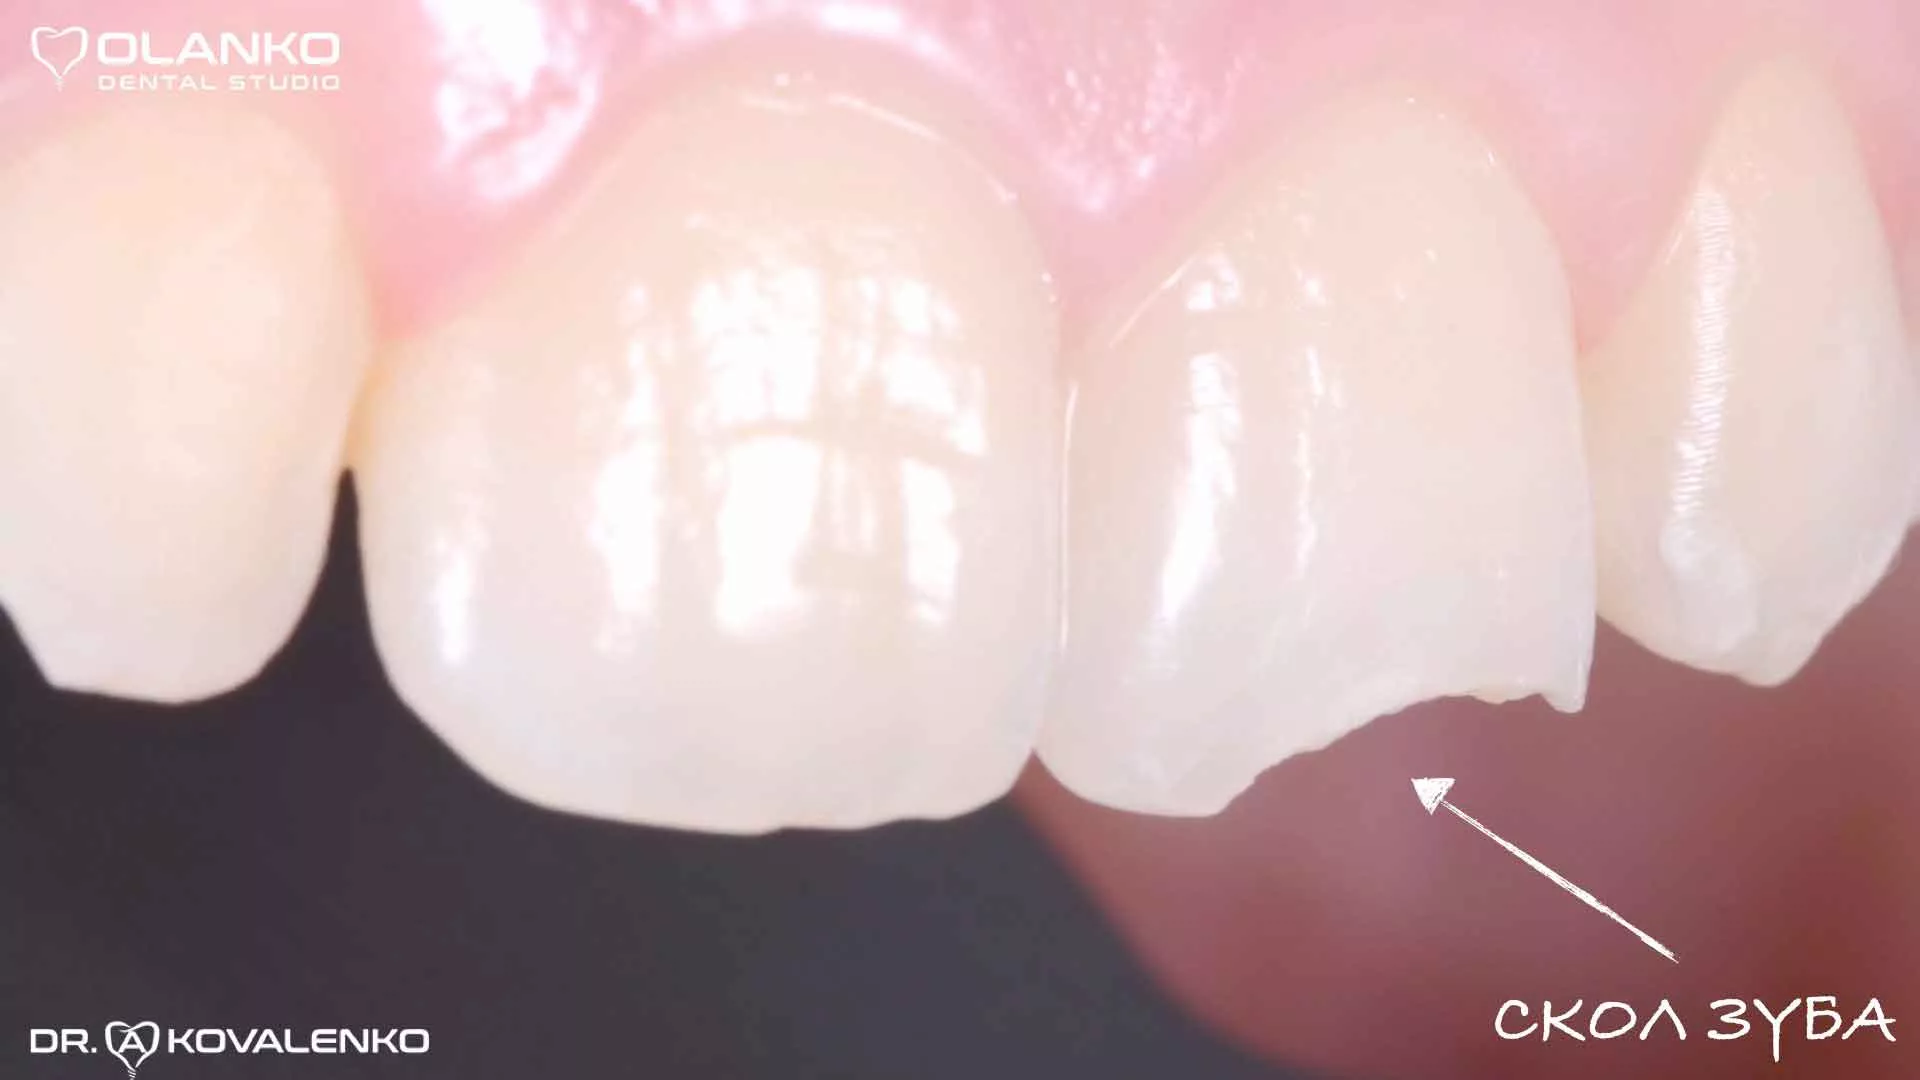

Основные показания к использованию этой технологии — это восстановление зубов, поражённых кариесом, а исправление не кариозных дефектов (травматические сколы, флюороз, гипоплазия).

Одновременно с преображением внешних данных зуба, надежно маскируются и его недостатки: сколы, трещины, небольшие дырки. Срок службы такого композита достигает 7 лет.

Реставрация фотополимером рекомендована пациентам с механическими травмами зуба и с другими незначительными отклонениями от нормы: